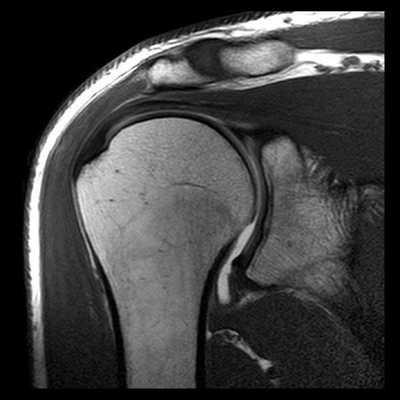

Вывих плеча на МРТ

Вывих плеча - одна из самых часто случающихся травм верхних конечностей. Он может быть первичным (свежим) и привычным. Магнитно-резонансная томография позволяет выявить повреждения в суставе и его связочном аппарате при обоих видах вывиха.

Первичный вывих плеча на МРТ

Первичный вывих плеча - это травма, возникшая, как правило, при механическом воздействии на сустав, в том числе, полученная в результате интенсивных физических нагрузок. Первичный вывих часто называют свежим. МРТ плечевого сустава визуализирует структуру сустава, соединяющего плечевую кость с костями, образующими пояс верхней конечности (ключица, лопатка), а также окружающих его тканей. На снимках, полученных в ходе МРТ, видны связки, мышцы, сухожилия, сосуды и нервы.

Привычный вывих плеча на МРТ

Привычный вывих плеча - одно из проявлений патологических процессов, происходящих в связочном аппарате сустава. Привычный вывих способна вызвать даже минимальная травма или повседневные действия. В таком случае обследование может быть проведено для определения степени разрыва капсулы сустава, связок и мышц или уточнения результатов рентгенографии и КТ, которые диагностируют повреждения костей наряду с МРТ. Признаками привычного вывиха плеча являются: травма сухожилий и подлопаточной мышцы, разрыв сегмента суставной губы и синовит. При вывихе МРТ необходима также для диагностики сдавливания сосудов и нервов плеча.